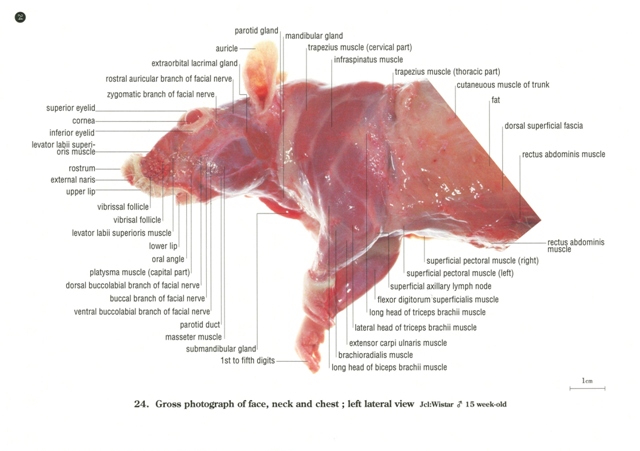

ラットの断面解剖アトラス。ラットの断面解剖アトラス - メルカリ。ラットの断面解剖アトラス。熊本県産ヒノヒカリ 30kg。 B 中古品としては綺麗と判断した商品。一般中古よりは状態の良い商品。 C 中古品として一般的な状態の商品。やや使用感があり、日焼けやキズなどがみられる場合がある商品。 D 中古品と考えても、気になる汚れやキズなどがある商品。。[A12303631]陽性・陰性症状評価尺度(PANSS)マニュアル。暫間ミニインプラント療法/永田睦(著者)。[A11078446]新生児学テキスト [単行本(ソフトカバー)] 一般社団法人 日本新生児成育医学会。改訂版・神経内科のスピード学習と専門医学習/泉義雄,五十棲一男【著】。[A12335451]徹底討論! ハートバルブ・カンファレンス。Ea-080/化学両方の領域 2016年4月号 Vol.32No.4 医薬ジャーナル社 2016年3月25日発行 特集:食の安全と微生物汚染 医療 医学 薬学/L1/61121。シノプティック・マテリア・メディカ 4訂/F.ヴァーミューラン(著者),RAH著(著者)。8K0098◆連続写真と動画で学ぶ 白内障手術パーフェクトマスター 基本から難症例への対処法まで 谷口重雄 ▽。[A01906937]すぐわかる小児の画像診断 改訂第2版 (画像診断別冊KEYBOOKシリーズ) [単行本] 荒木 力、 原 裕子; 野坂 俊介。IVR-手技,合併症とその対策 Interventional/石橋忠司(著者),山田章吾(著者)。眼光学 1 眼内レンズ/市川宏(著者)。[A11048022]造血器腫瘍アトラス 形態、免疫、染色体から分子細胞治療へ 谷脇 雅史、 横田 昇平; 黒田 純也。カラー図解 脳神経ペディア 「解剖」と「機能」が見える・つながる事典/渡辺雅彦(著者)。培養細胞実験ハンドブック 改訂 基本から最新の幹細胞培養法まで完全網羅!/黒木登志夫(著者),許南浩(著者)。[A01564935]病院の世紀の理論。機能性食品の作用と安全性百科/上野川修一(著者)。[A01351009]ICUブック 第4版。整形外科スタンダード手術基本手技/山本眞(著者)。H19-047 醫學博士 茂木藏之助 著 茂木外科總論 南山堂 書き込みあり。。胃 形態とその機能 第2版 形態とその機能/川井啓市(著者)。[A12326342]リウマチ・膠原病アトラス 廣畑 俊成。日経デジタルヘルス年鑑(2017)/日経デジタルヘルス。[A12090911]硬膜動静脈瘻塞栓術ハンドブック [単行本] 滝 和郎。[A11248770]一歩進んだ麻酔管理~常識は常に真実か?~ 国沢 卓之。[A12333909]睡眠とてんかん: その密接な関連性。[A12335621]バスキュラーアクセスのトラブルシューティング ─ 電子版付 ─。[A12344518]改訂第6版 救急診療指針 上巻 (上巻)。ネッター解剖学図譜 第2版/相磯貞和(著者)。[A01204523]EBMによる糖尿病経口薬の選択と適正使用。【まとめ/訳あり】緑内障 11冊セット 眼科/診療/薬物治療/ガイドブック/【2211-041】。[A12325943]不整脈 識る・診る・治す (循環器内科専門医バイブル) [単行本] 平尾見三; 小室一成。[A11760723]領域横断的がん取扱い規約。[A12325147]イラストでイメージする 小児の心エコー 第2版 (第2版)。眼科手術学/ゲオルク・アイスナー(著者),渡辺郁緒(著者)。[A12309814]診断と治療2019年増刊号。[A12357725]頭頸部がん手術ノート 輪層の外科。[A11067697]CTパターンから理解する呼吸器疾患: 所見×患者情報から導く鑑別と治療 門田 淳一。★カラーフォト皮膚病1★籏野 倫★。胸部CTの異常陰影/松原義人(著者)。[A12301703]オルソケラトロジ-・ハンドブック トッド・D.ウィンクラ-、 ロジャ-・T.ケイム; 日本オルソケラトロジ-協会。[A12343460]小児画像診断の勘ドコロNEO。DVD SPAT 頚椎・胸椎編/鹿島田忠史(著者)。[A11550186]腸疾患診療―プロセスとノウハウ。和蘭薬鏡(全) 科学書院。脳神経外科臨床マニュアル 改訂第5版/端和夫(編者),三國信啓(編者)。[A11185929]脊椎・骨盤の外傷手技のコツ&トラブルシューティング [DVD付] (OS NOW Instruction)